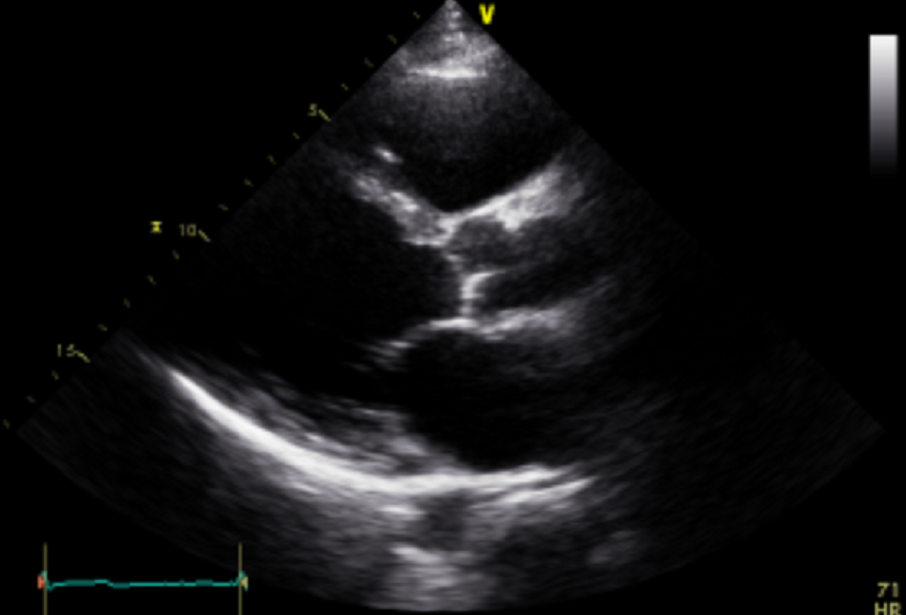

심장질환 분야에서 가장 보편적으로 활용되고 있는 심초음파 검사와 관련하여 다양한 AI 연구개발에 활용될 수 있는 관련 임상의료데이터 및 경흉부 X-ray 데이터

정확하고 효율적인 의료서비스를 지원하는 AI기술 개발이 가능하도록 심장질환 분야에서 일차적으로 활용되는 심전도 및 심초음파 데이터와 그 활용성을 극대화 할 수 있는 유관 데이터를 포함하는 ‘학습용 표준 빅데이터’를 구축

| 원천데이터(DICOM) |

![]() |

| id | "0118610_echo_001" |

| filename | "0118610_echo_001.dcm" |

| width | 636 |

| height | 434 |

| study date | “2018.03.26” |

| patient_id | “0118610” |

| disease_category | “1” |

| view_category | 0 |